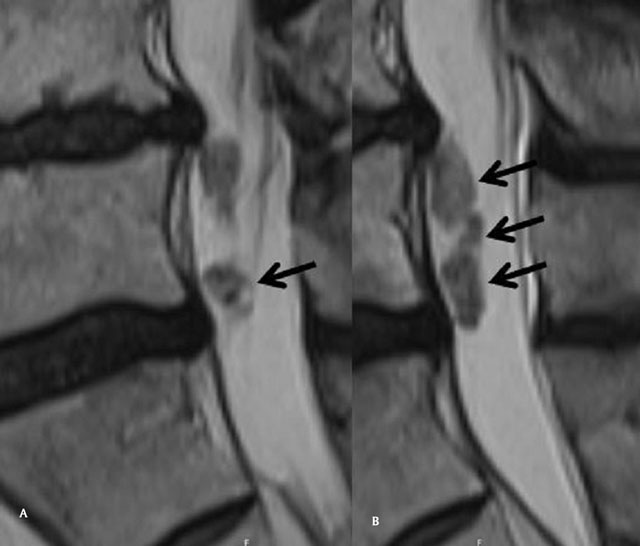

Figure 2A,B

Sagittal T2 Mri of the lumbar spine, “crumbled” aspect of the intradural component of the IDH (arrows).